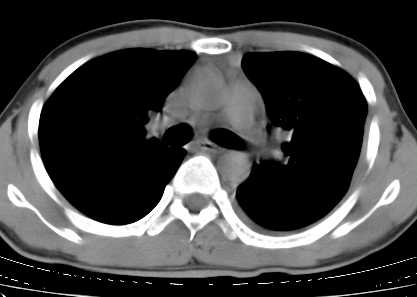

二周前患者无明显诱因出现咳嗽,多为刺激性干嗽,无咯血,伴心悸,低热,夜间无明显盗汗,消瘦明显

年龄?左侧胸腔中量积液,左下肺见有较多斑片状和大片状影,伴有支气管充气征,考虑:1、左下肺炎;2、结核。肿瘤可以基本排除。

考虑:1、左下肺结核左侧胸腔中量积液,心包积液纵隔肿大淋巴结.

考虑:1、左侧中量胸腔积液伴左肺下叶肺膨胀不全、炎症。

2、心包积液。

左侧中量胸腔积液伴左肺下叶肺膨胀不全、上肺外围多个小囊样腺泡样病灶。考虑化脓炎症。

心包积液没有,纵隔积液。

1、左侧中量胸腔积液伴左肺下叶肺膨胀不全、。

左肺舌叶及下叶见斑片状,大片状高密度影并相应处胸膜及心包不规则增厚,左肺下叶膨胀不全。右肺未见异常,双肺段以上支气管通畅。纵隔左移,其内未见明显肿大淋巴结。左侧胸腔积液。

1.考虑:左肺化脓性炎症。2.左侧胸腔积液(中等量)。3.心包炎症。